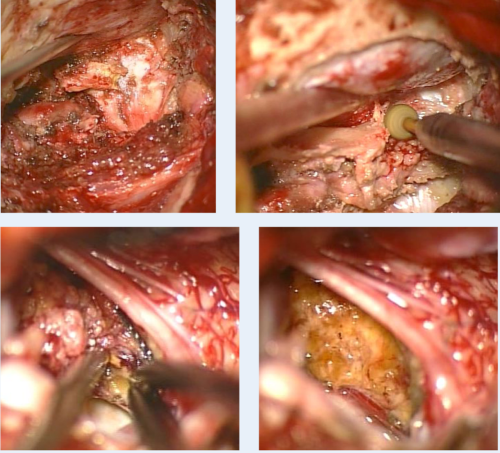

手術(shù)入路 腦干延髓海綿狀血管瘤

患者半坐位,及體表手術(shù)入路切口標(biāo)記

腦干延髓海綿狀血管瘤案例

巴教授親自行遠(yuǎn)外側(cè)入路開(kāi)顱Craniotomy